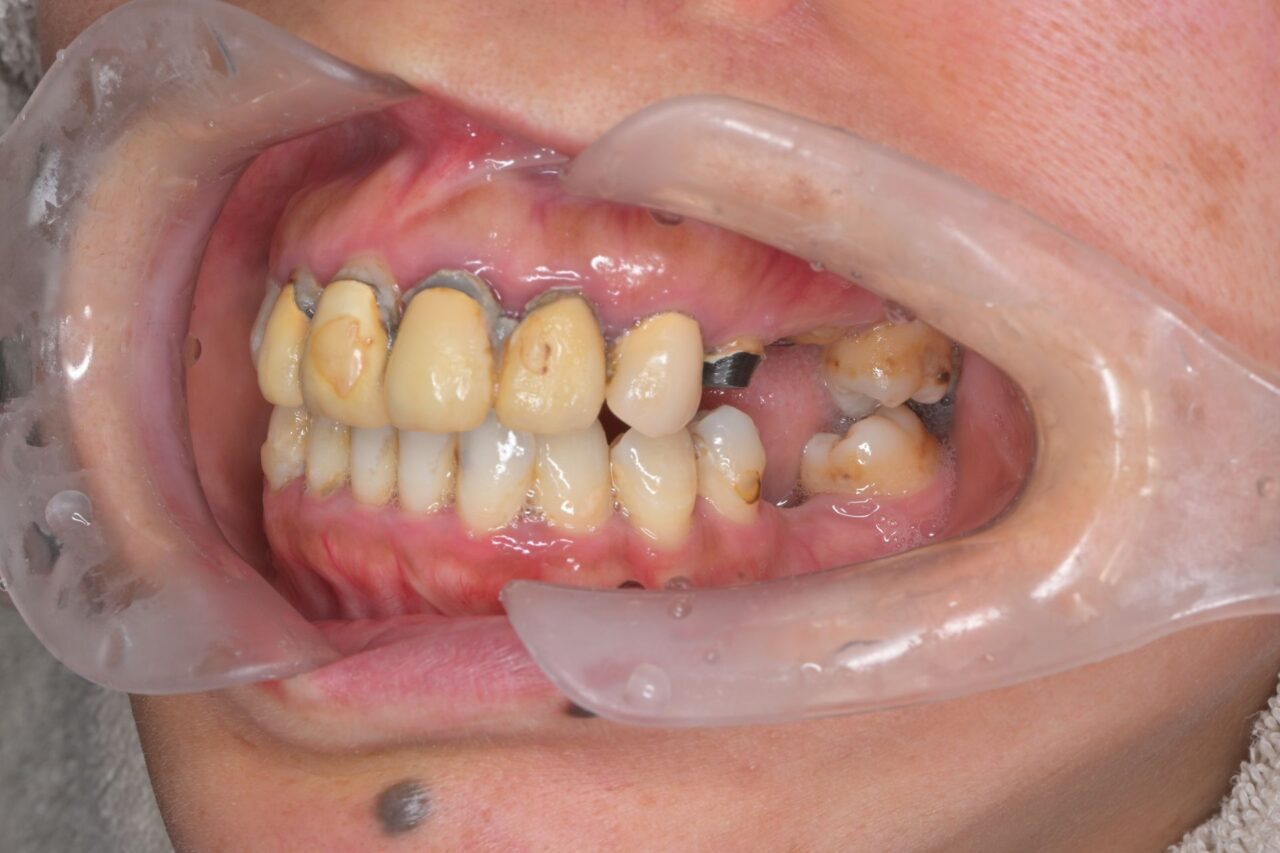

左側面

左右共に奥歯が無いので、歯の支えが全く無い状態です。これでは、お肉などを噛むことが出来ません。

さらに、舌も肥大化してしまっていますねぇ。

「前歯があるじゃん。」と思うかもしれませんが、前歯はうどんなどの柔らかいものを噛み切るための物で、決して硬いものを噛むための歯ではありません。柔らかい物ばかりを食べていると炭水化物が多くなってしまい糖尿病にもなりやすくなります。大切なのは奥歯です。